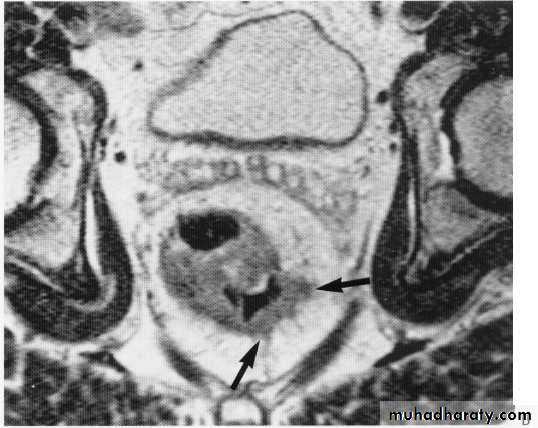

Rectal tumor with local invasion